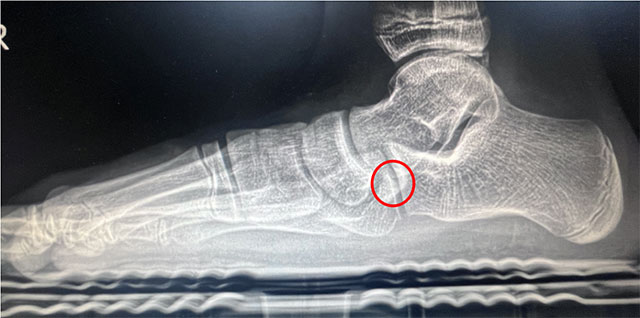

2024年6月13日,西南医科大学附属中医医院骨伤科关节·足踝组张磊博士门诊接诊了一名扁平足的初中生。14岁的小莉走路过程中足底有疼痛感,长时间走路后会感觉足底肿胀,遂来医院就诊,被诊断为“右足副舟骨痛+右足扁平足”,张磊博士团队考虑小莉实际情况,经微创治疗距下关节制动术后,小莉疼痛症状缓解。

12月1日,小莉再次来到骨伤科关节·足踝组复查,外观可见扁平足改善效果明显。

部分青少年患者可选择放入距下关节制动器,改善距下关节活动,缓解疼痛,一定程度改善足的外观及畸形。可联合进行副舟骨切除和胫后肌腱止点重建术。